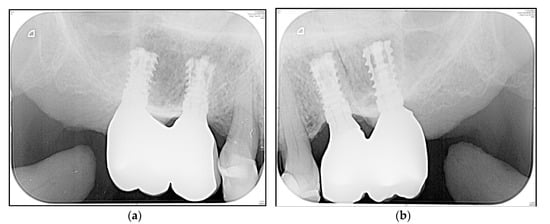

3.4. Crestal Bone Changes